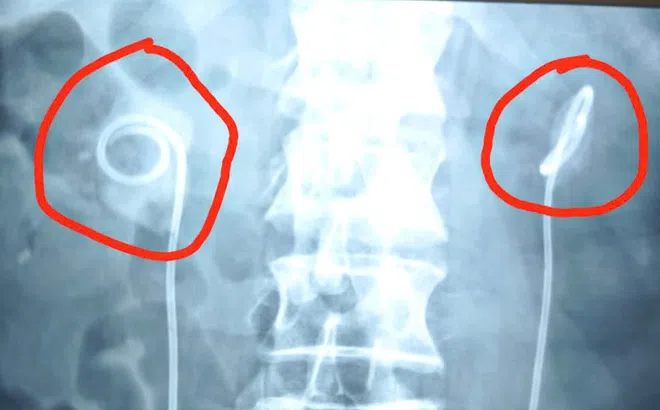

Quên rút ống thông niệu quản suốt 2 năm, người đàn ông biến chứng nặng nề

Bệnh viện Bệnh nhiệt đới trung ương vừa tiếp nhận và xử lý thành công trường hợp bệnh nhân L.K.T. (64 tuổi, Hà Nội) gặp biến chứng nặng nề do để “quên” sonde JJ, hay còn gọi là ống thông niệu quản đôi chữ J, quá hạn 2 năm.